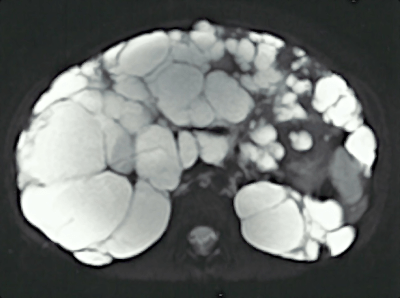

- Doença hepática policística

Fígado aumentado por múltiplos cistos na doença policística hepática (publicado com consentimento da paciente)